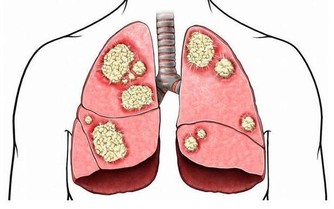

眾所周知,一旦尿酸高了,會引發全身性疾病,首當其衝的就是關節疾病,對於腎臟、血管等都會有不同程度的損害,還會影響血糖引發糖尿病等等。

睡覺之前出現排尿異常情況,那麼也有可能是尿酸過高導致的,因為腎臟有問題,尿液就會出現異常,睡覺之前小便的時候會發現尿液的顏色是很濃的茶水色,甚至會出現泡沫樣,這就是因為尿酸鹽的結晶堆積所引起的,會影響到尿液的顏色以及形態,而且小便次數也會受到影響。如果你經常出現這樣的情況,很有可能就是腎臟出現了問題,一定要及時的觀察。

晚上睡覺的時候身體裡面的尿酸含量是最高的,所以腎小球容易被堵塞,甚至會出現壞死情況,身體裡面的水分沒有辦法很好的排出,容易堆積在身體裡面,這樣就會出現水腫情況,特別是下肢水腫以及眼瞼水腫的情況是比較嚴重的。